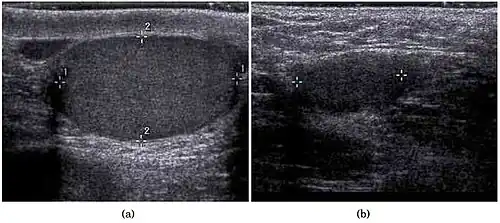

In the minority of cases with bilaterally nonpalpable testes, further testing to locate the testes, assess their function, and exclude additional problems is often useful. Scrotal ultrasound or magnetic resonance imaging performed and interpreted by a radiologist can often locate the testes while confirming the absence of a uterus. At ultrasound, the undescended testis usually appears small, less echogenic than the contralateral normal testis and usually located in the inguinal region. With color Doppler ultrasonography, the vascularity of the undescended testis is poor.